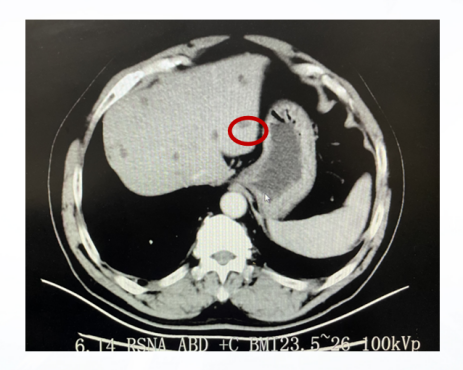

影像学检查:

胸部增强CT:右肺中叶小结节(5mm);纵隔淋巴结钙化;冠状动脉硬化。

上腹部增强CT:肝脏多发囊肿;右肾结石;横结肠肠套叠。

下腹部增强CT:未见明显异常。

图10、胸部增强CT(2014-12-04)

图11、腹部增强CT(2014-12-04)

图12、腹部增强CT(2014-12-04)